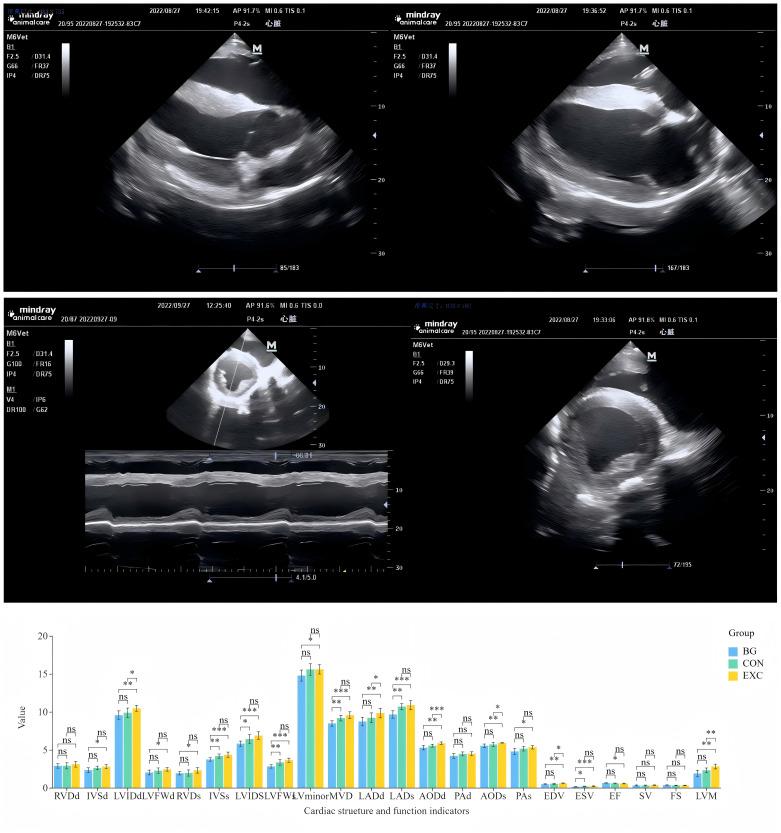

Yili horses, a versatile breed from Xinjiang, China, are renowned for their racing abilities. However, studies on the links between cardiac morphology, function, and metabolic profiles with performance are limited. This study combined echocardiographic, transcriptomic, and metabolomic analyses to explore these relationships in high-level, average, and untrained Yili horses. Echocardiographic assessments revealed increased left ventricular mass in trained horses, with significant differences in intraventricular septal thickness and left ventricular end-diastolic diameter. RNA sequencing identified 534 differentially expressed genes, 366 differentially expressed miRNAs, highlighting pathways in glycine, serine, and threonine metabolism, oxygen transport (e.g., ALAS2), and ATP generation. Metabolomic analysis revealed variations in acylcarnitine and triglycerides, suggesting training-induced cardiac remodeling regulated by miRNAs. This integrated approach provides new insights into the molecular and metabolic factors influencing performance, offering a foundation for optimized training strategies for Yili horses.

摘要

伊犁马是一种来自中国新疆的多功能马种,以其赛跑能力而闻名。然而,关于心脏形态、功能和代谢谱与性能之间联系的研究有限。本研究结合超声心动图、转录组学和代谢组学分析,以探索高水平、中等水平和未经训练的伊犁马之间的这些关系。超声心动图评估显示,训练有素的马匹左心室质量增加,室间隔厚度和左心室舒张末期直径存在显著差异。RNA测序确定了534个差异表达基因、366个差异表达的miRNA,突出了甘氨酸、丝氨酸和苏氨酸代谢、氧运输(如ALAS2)和ATP生成中的途径。代谢组学分析揭示了酰基肉碱和甘油三酯的变化,表明训练诱导的心脏重塑受miRNA调节。这种综合方法为影响性能的分子和代谢因素提供了新的见解,为伊犁马优化训练策略提供了基础。